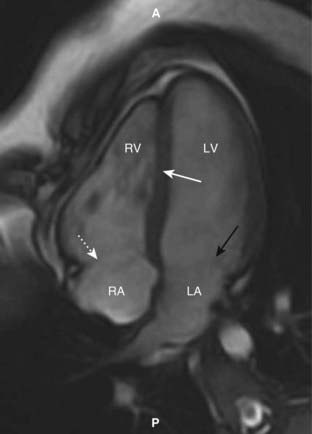

image

Figure 9-30 Cardiac MRI, horizontal long axis view.

This is another standard view of the heart using MRI called the horizontal long axis or four-chamber view. The right (RV) and left ventricles (LV) are separated by the interventricular septum (solid white arrow). Posterior to each of them are the right atrium (RA) and left atrium (LA) separated by the regions of the tricuspid (dotted white arrow) and mitral valves (solid black arrow), respectively. (A is anterior and P is posterior.)